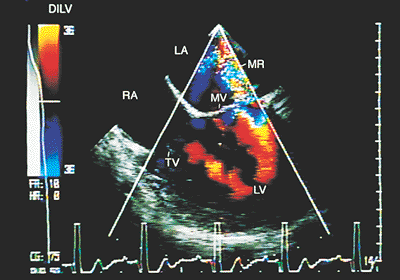

Recordings with the different Doppler techniques allow the diagnosis of stenosis or regurgitation of the A–V valves (Fig. 8.2.32). They also help recognize defects of the interatrial septum or its absence (common atrium).

The echocardiographic characteristics of the double inlet of the right ventricle have a great deal in common with those of the double inlet of the left ventricle, with the difference that the two A–V valves, or the common A–V valve, are always visualized in a position anterior to the trabecular septum. The rudimentary ventricle is posterior in relation to the main ventricle. The posterior A–V valve often straddles the interventricular septum with insertions in the rudimentary ventricle.

FIGURE 8.2.32. Double inlet ventricle. Four-chamber imaging with color Doppler demonstrates mitral regurgitation (MR) in a patient with double inlet left ventricle (DILV). LA, left atrium; LV, left ventricle; MV, mitral valve; RA, right atrium; TV, tricuspid valve.